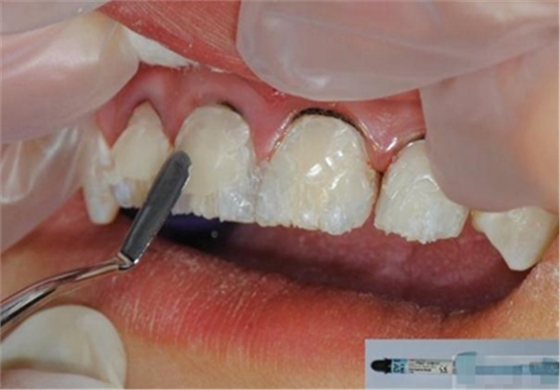

【初步修整】

對(duì)于唇面,首先使用火焰狀車針進(jìn)行修整,一般不使用輪狀車針修整線角

微細(xì)的表面結(jié)構(gòu)最后使用鎢鋼拋光車針成形的。

修整完成

拋光目的:表面光滑 咬合關(guān)系 邊緣適應(yīng) 最少的菌斑附著 易于菌斑去除 美觀性

【纖維刷拋光】

【充填完成】

1、樹(shù)脂貼面平齊牙齦邊緣是最佳設(shè)計(jì),或者使用齦上邊緣 。

2、釉質(zhì)邊緣要用橡皮輪拋光。拋光可以去除懸釉。這樣經(jīng)過(guò)車針打磨過(guò)的釉質(zhì)表面會(huì)更加均一,形成良好的邊緣封閉。